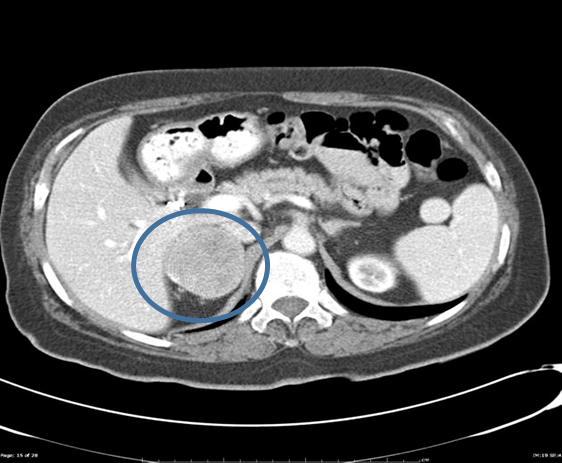

When do you treat non-functional incidentalomas?

Nonfunctional Incidentalomas are often round and well circumscribed with heterogenous enhancement on imaging

You treat them based on their size and imaging characteristics

1) Small (less than 3 cm) you observe

2) > 4 cm you should surgically resect due to risk of adrenocortical carcinoma

3) in between 3-4 cm you should surveillance with imaging and labs

→ you can resect if good candidate